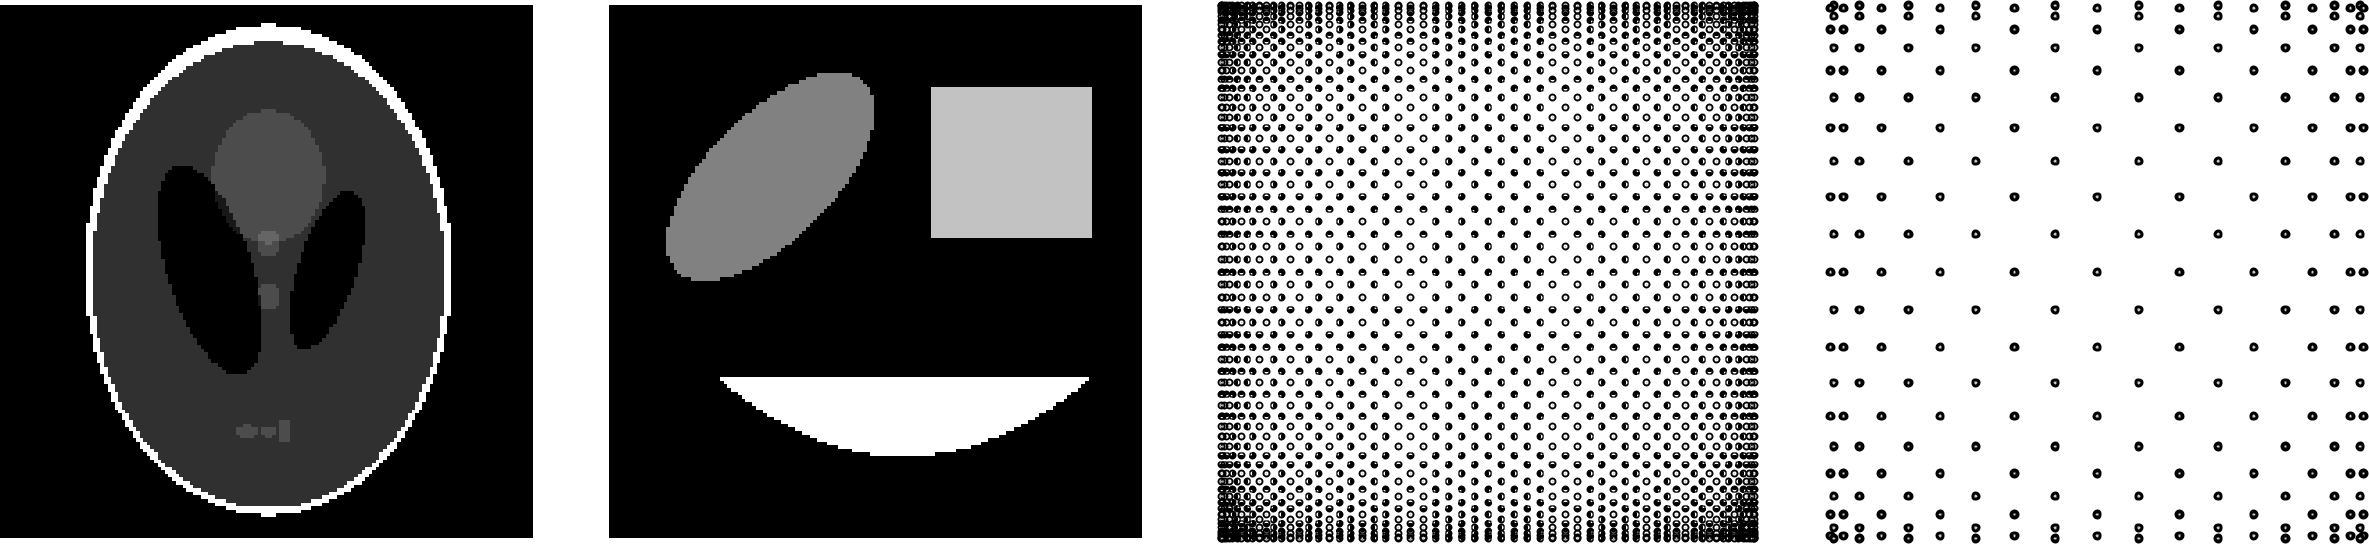

In our main application in magnetic particle imaging we will use samples along Lissajous trajectories as interpolation nodes. For this, we will introduce and use these node sets already for the numerical experiments in this section. As test images we consider the Shepp-Logan phantom and an additional simple geometric phantom. We give a brief description of this experimental setup.

Refer to caption

Figure 1: The Shepp-Logan phantom (left), a geometric phantom (middle, left), as well as the Lissajous nodes 𝐋𝐒2(32,33)superscriptsubscript𝐋𝐒23233\bm{\mathrm{LS}}_{2}^{(32,33)} (middle, right) and 𝐋𝐒2(10,11)superscriptsubscript𝐋𝐒21011\bm{\mathrm{LS}}_{2}^{(10,11)} (right).

For 𝒏=(32,33)𝒏3233\bm{n}=(32,33) and 𝒏=(10,11)𝒏1011\bm{n}=(10,11), the nodes 𝐋𝐒2(𝒏)superscriptsubscript𝐋𝐒2𝒏\bm{\mathrm{LS}}_{2}^{(\bm{n})} are illustrated in Figure 1 (right).

4.1.2 Shepp-Logan phantom

As a main test phantom with sharp edges, we use the Shepp-Logan phantom fSLsubscript𝑓SLf_{\mathrm{SL}} on Ω=[1,1]2Ωsuperscript112\Omega=[-1,1]^{2} as introduced in [36]. The function fSL:[1,1]2[0,1]:subscript𝑓SLsuperscript11201f_{\mathrm{SL}}:[-1,1]^{2}\to[0,1] is defined as a composition of 101010 step functions determined by elliptic equations. A discretization of fSLsubscript𝑓SLf_{\mathrm{SL}} on an equidistant M×M𝑀𝑀M\times M grid, M=150𝑀150M=150, is displayed in Figure 1 (left).

4.1.3 Geometric phantom

As a second phantom we use a geometric composition fGsubscript𝑓Gf_{\mathrm{G}} of an ellipse EE\mathrm{E}, a rectangle RR\mathrm{R} and a bounded parabola PP\mathrm{P}, discretized on a M×M𝑀𝑀M\times M grid of size M=150𝑀150M=150. The function fGsubscript𝑓Gf_{\mathrm{G}} on Ω=[1,1]2Ωsuperscript112\Omega=[-1,1]^{2} is given as fG=χE+1.5χR+2χPsubscript𝑓Gsubscript𝜒E1.5subscript𝜒R2subscript𝜒Pf_{\mathrm{G}}=\chi_{\mathrm{E}}+1.5\chi_{\mathrm{R}}+2\chi_{\mathrm{P}}, where χEsubscript𝜒E\chi_{\mathrm{E}}, χRsubscript𝜒R\chi_{\mathrm{R}} and χPsubscript𝜒P\chi_{\mathrm{P}} denote the characteristic functions of EE\mathrm{E}, RR\mathrm{R} and PP\mathrm{P}, respectively. The phantom fGsubscript𝑓Gf_{\mathrm{G}} is illustrated in Figure 1 (middle, left).